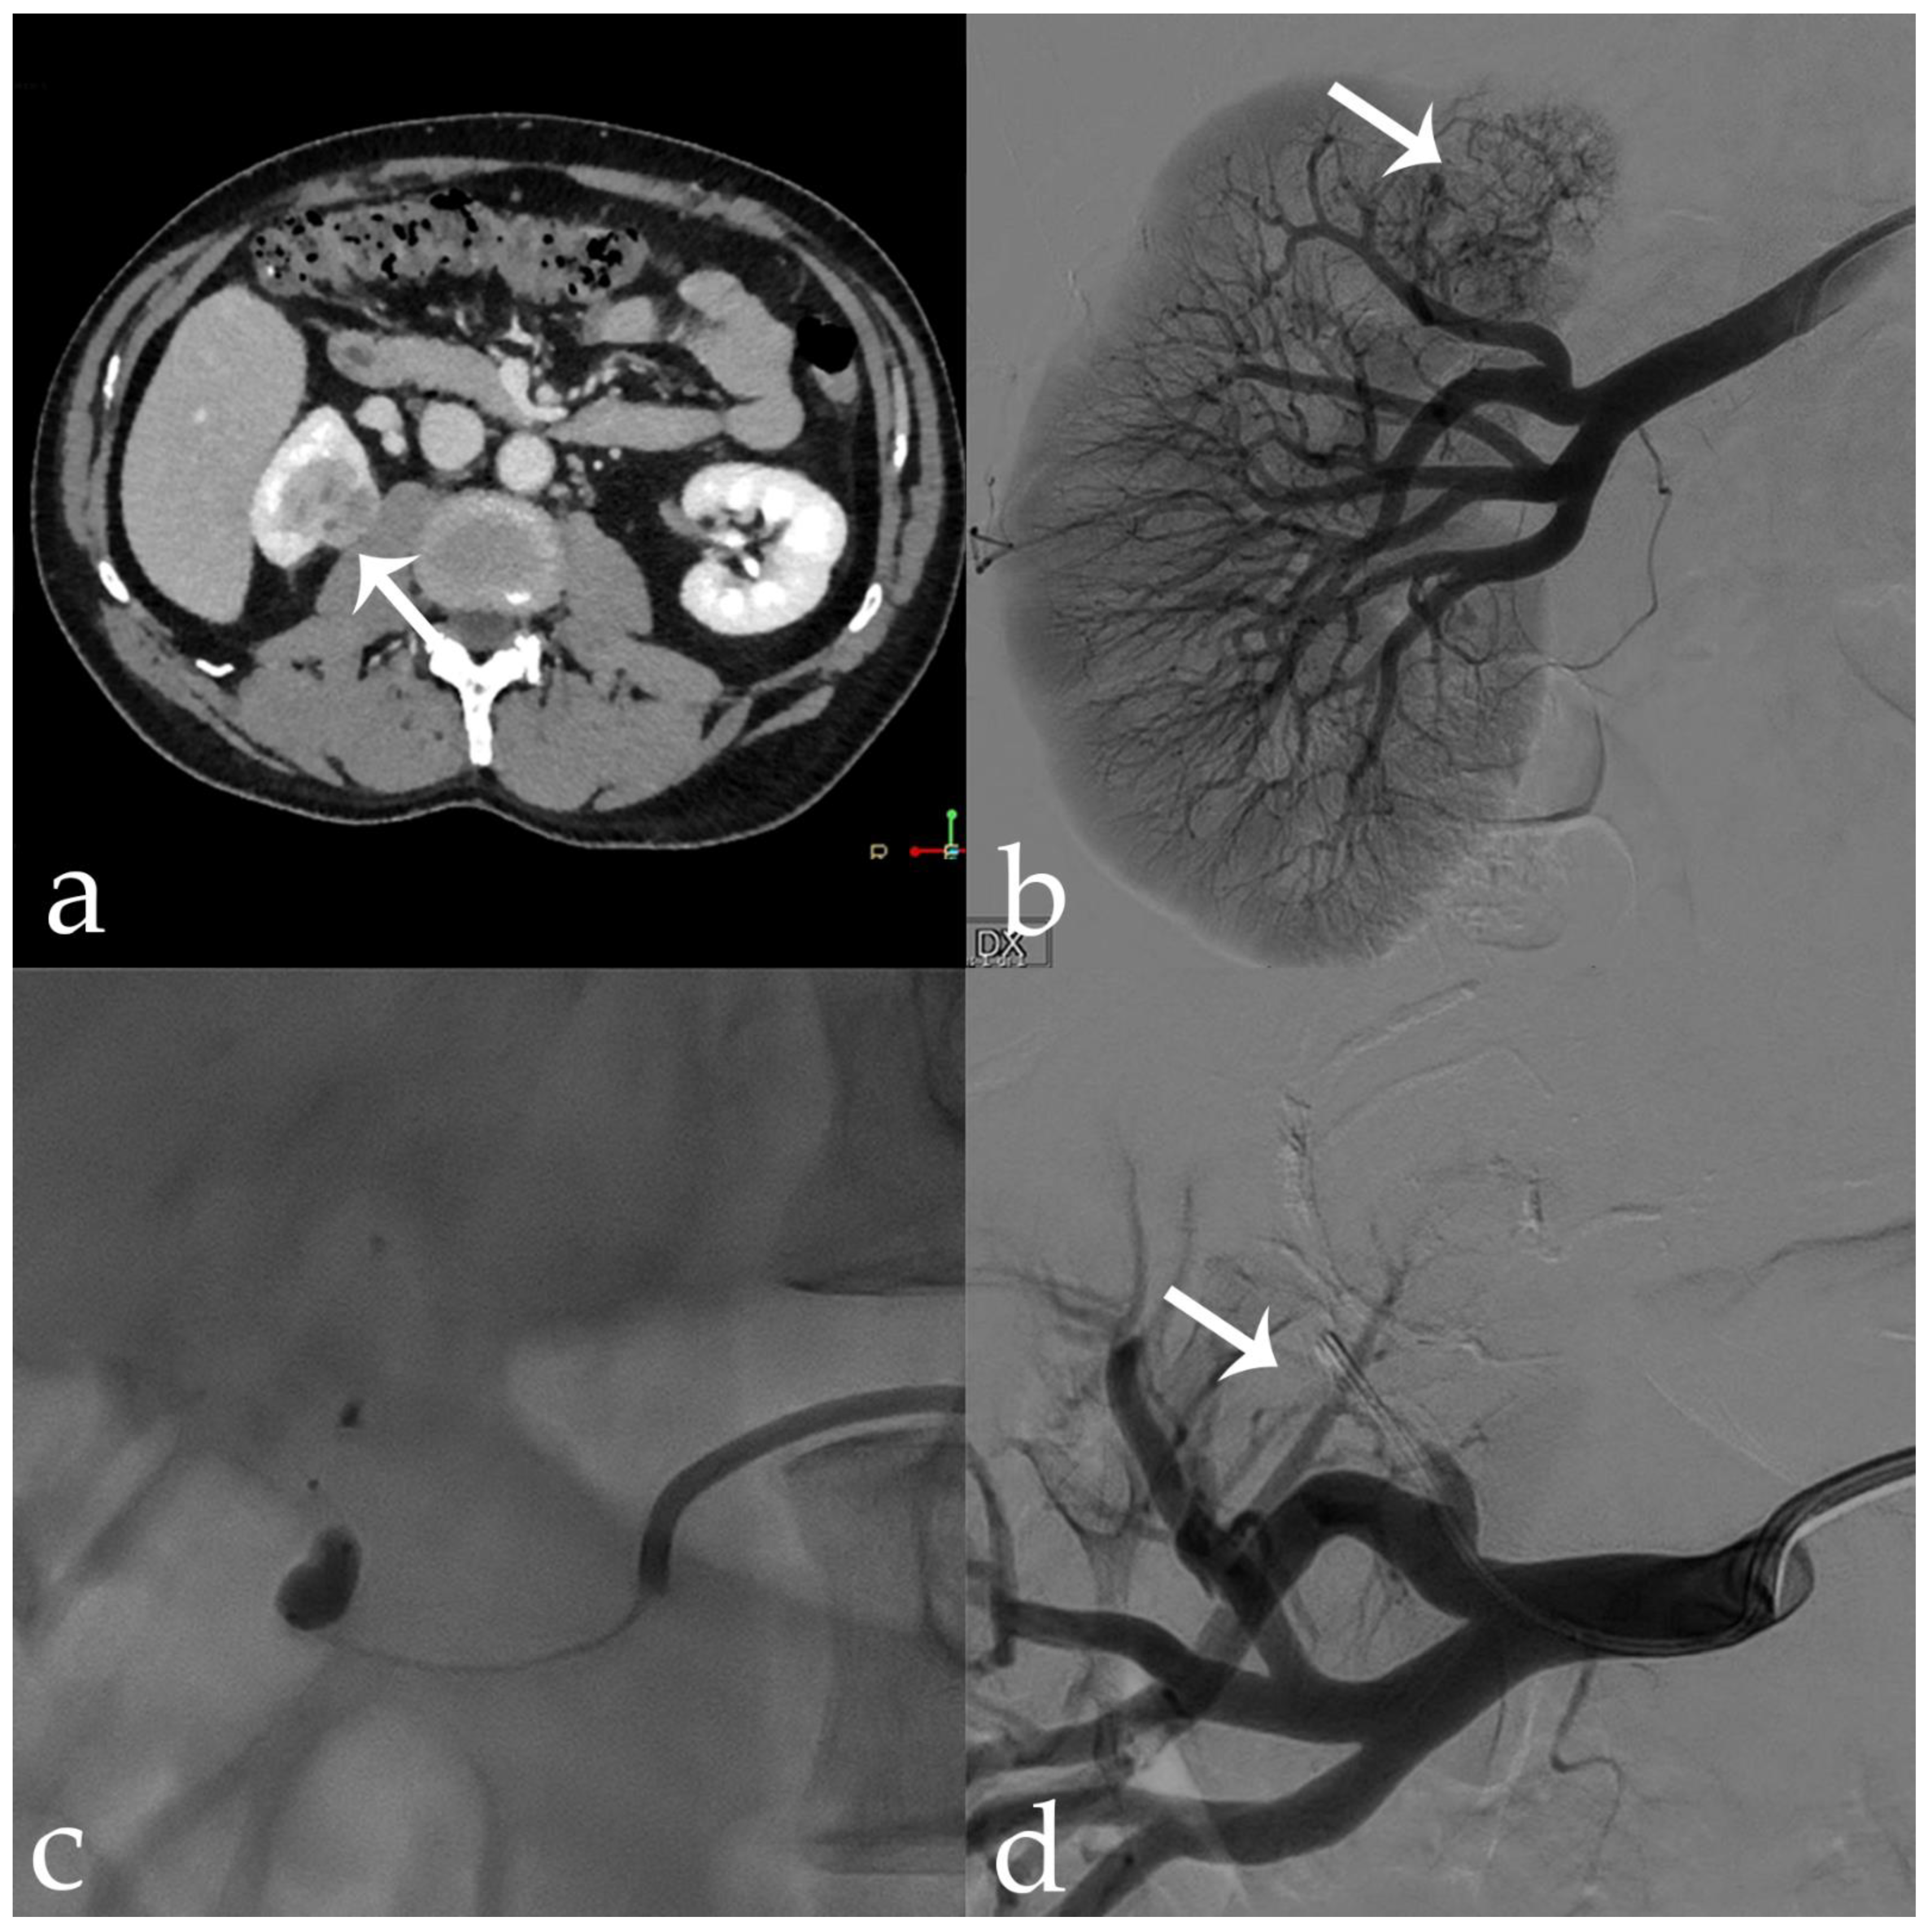

Figure 6. 56 yr old male with endo-exophytic RCC of the right kidney upper pole (30 × 20 mm): (a) pre-operative CECT; (b) pre-embolization DSA showing tumor vascular supply (arrow); (c) embolization procedure using stop-flow technique after super selective setting with a microcatheter-balloon inflated during 18-Onyx and indocyanine mixture administration; (d) post-procedural DSA showing complete tumor devascularization (arrow).